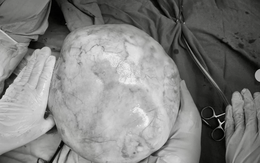

Mới đây, tại Bệnh viện Phụ sản Trung ương, các bác sĩ khoa phụ ung thư vừa tiếp nhận và điều trị thành công một trường hợp bệnh nhi 14 tuổi với khối u buồng trứng khổng lồ nặng tới 4,3kg, một ca bệnh hiếm gặp tiềm ẩn nhiều nguy cơ nghiêm trọng.